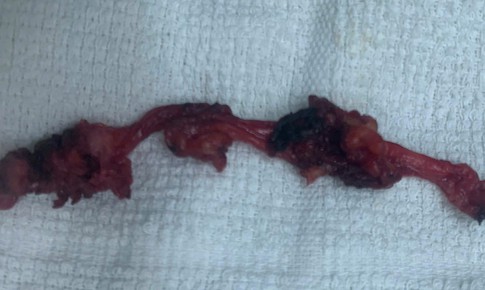

SKĐS - Bác sĩ Khoa Ngoại – Gây mê hồi sức, Trung tâm Y tế khu vực Cẩm Mỹ (Đồng Nai) đã tiếp nhận và phẫu thuật nội soi thành công một trường hợp nang niệu rốn, một bệnh lý hiếm gặp.